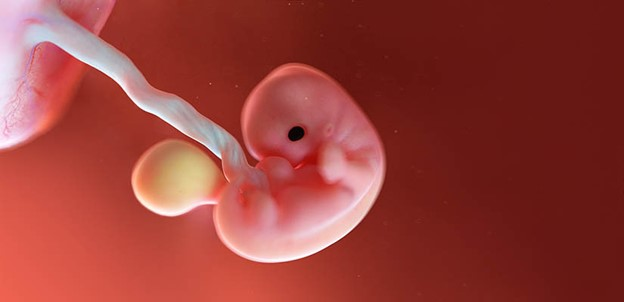

Развитие эмбриона

Будущий малыш на третий акушерский месяц представляет собой микроскопический шар из множества клеток, называемых бластоцистой. Размер эмбриона на данном этапе сравним с булавочной головкой, однако уже начинают происходить важные процессы: формирование органов и систем.

Ваш ребенок на третьей неделе беременности: первые шаги в жизнь

На третьи сутки беременности эмбрион состоит из сотни клеток, активно делящихся и развивающихся. Внешние слои клеток образуют будущую плаценту, обеспечивающую питание и защиту ребёнка, а внутренняя группа клеток станет основой будущих органов и тканей.

Несмотря на маленькие размеры, каждая клеточка важна и играет свою роль в формировании здорового малыша. Пока ребёнок продолжает расти и делиться, он незаметно движется вперёд, медленно формируя свое будущее тело.